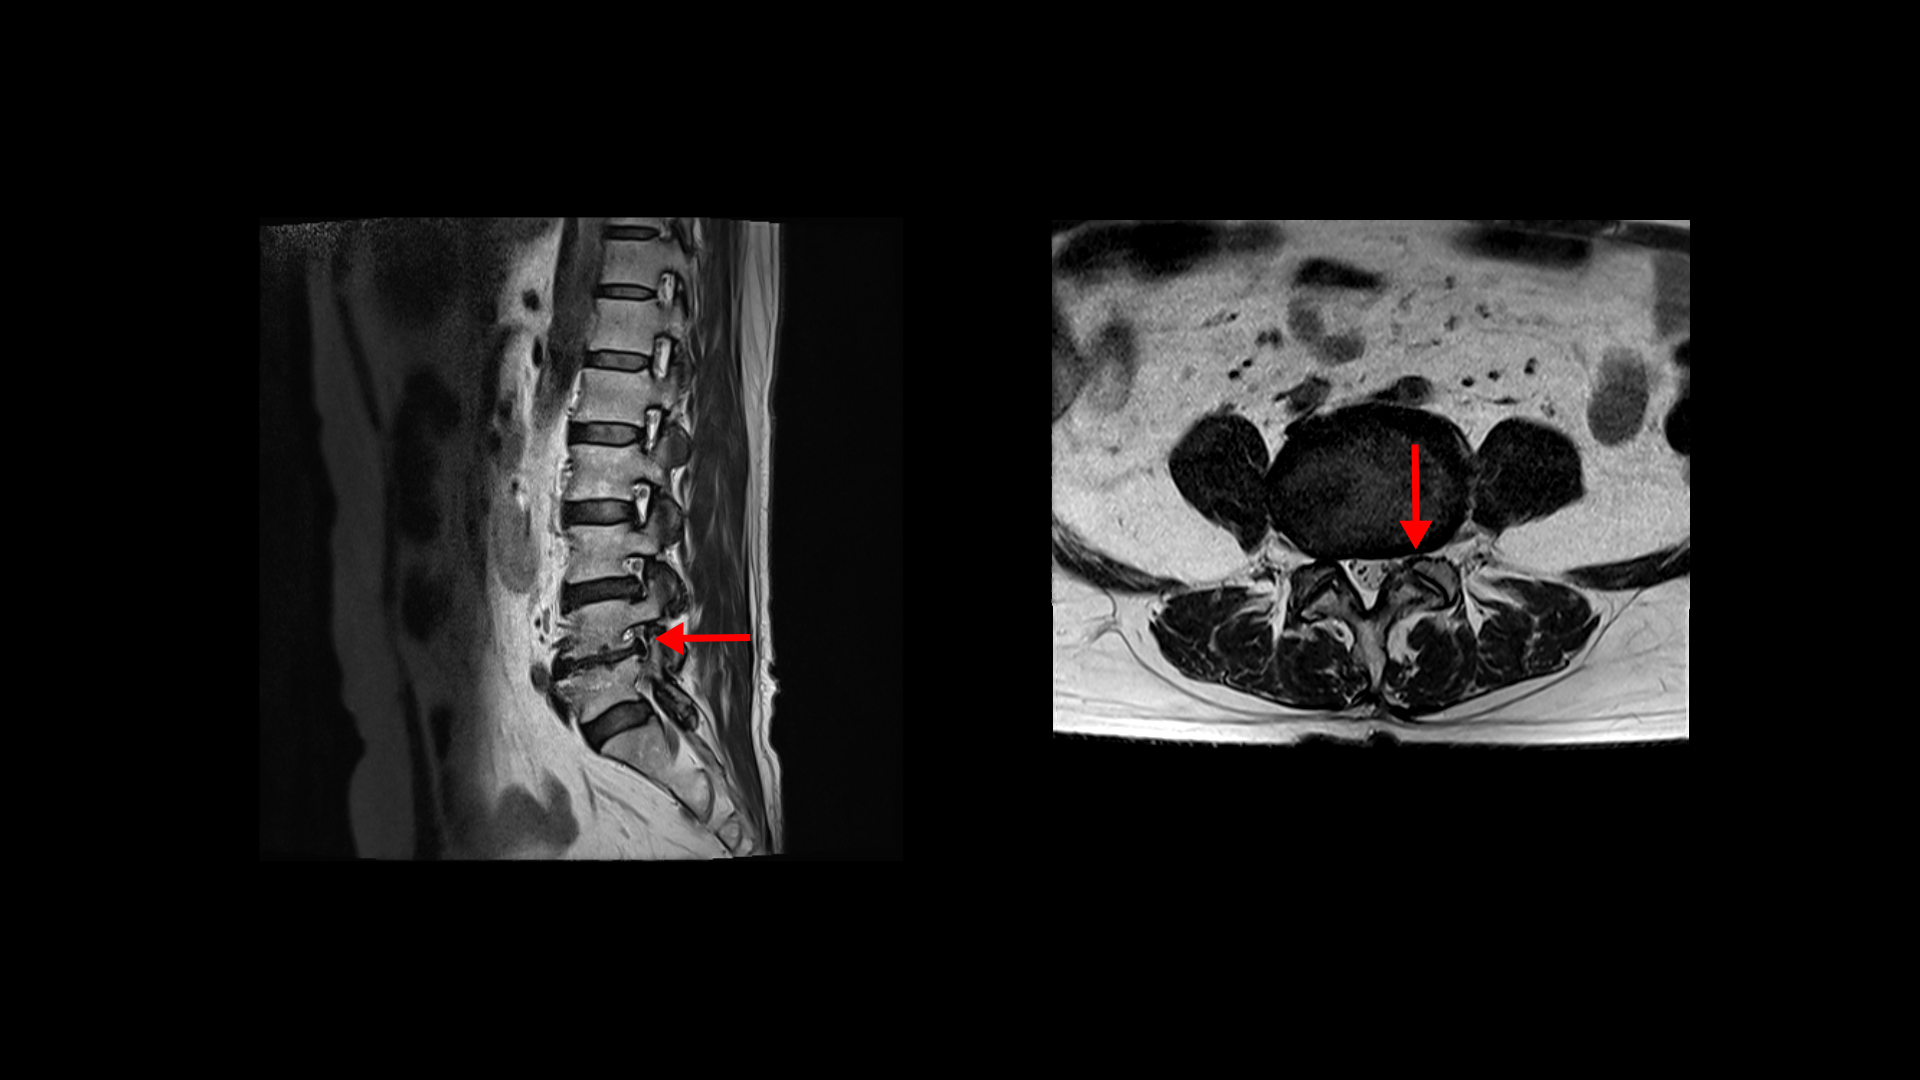

제가 먼저 이 환자분의 상태에 대해 설명드린 후 이분 말씀 더 들어보겠습니다. 이 환자분은 정말 오래된, 본인 표현으로는 30년된 심한 여러 마디의 목디스크와 또 허리에는 2마디의 퇴행성 디스크 및 추간공협착이 있습니다. 목디스크는 MRI로 보면 3번 4번 목디스크가 뼈가 심하게 자라면서 밀려나와있고 왼쪽으로 나가는 신경길을 막고 있습니다.

5번 6번 디스크도 왼쪽으로 심하게 밀려나와 있습니다. 이분 왼쪽 팔의 힘 빠짐 증상은 이것 때문인 것으로 보입니다.

허리MRI를 보면 두 마디의 퇴행성디스크와 추간공협착이 있습니다.

3번 4번은 왼쪽 중앙으로 밀려나와있고

4번 5번은 왼쪽 신경이 빠져나가는 추간공이 뼈가 자라면서 좁아져 추간공협착이 있습니다.

또 왼쪽 후궁에는 과거에 받은 수술의 흔적도 보입니다.